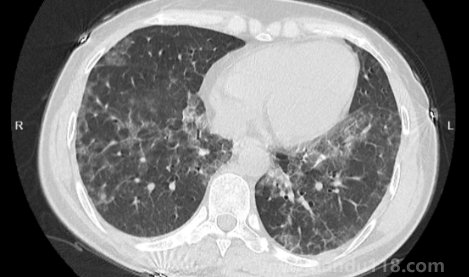

新冠白肺可逆嗎(新冠肺部白化能恢復(fù)嗎) 新冠白肺可逆嗎(新冠肺部白化能恢復(fù)嗎)新冠白肺是比價(jià)常見的一個(gè)癥狀,現(xiàn)在無論老人還是年輕人如果新冠感染一直咳又不康復(fù)的話,可能會出現(xiàn)白肺或者肺炎的情況。那么,新冠白肺可逆嗎?84歲老人肺全白有救嗎?一... 小編 2023-01-09 889 #新冠 #白肺

如何自查是否出現(xiàn)白肺(肺白了還能恢復(fù)嗎) 如何自查是否出現(xiàn)白肺(肺白了還能恢復(fù)嗎)白肺是目前很常見的情況,受新冠影響很多老年人都出現(xiàn)了白肺的情況,當(dāng)然也有年輕人會患上白肺。那么,如何自查是否出現(xiàn)白肺?平時(shí)怎樣保護(hù)自己的肺?一起來看看天都生活網(wǎng)... 小編 2023-01-06 874 #白肺